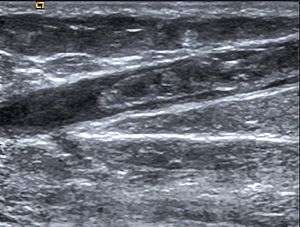

| Radiological image showing thrombosis of the great saphenous vein. | |